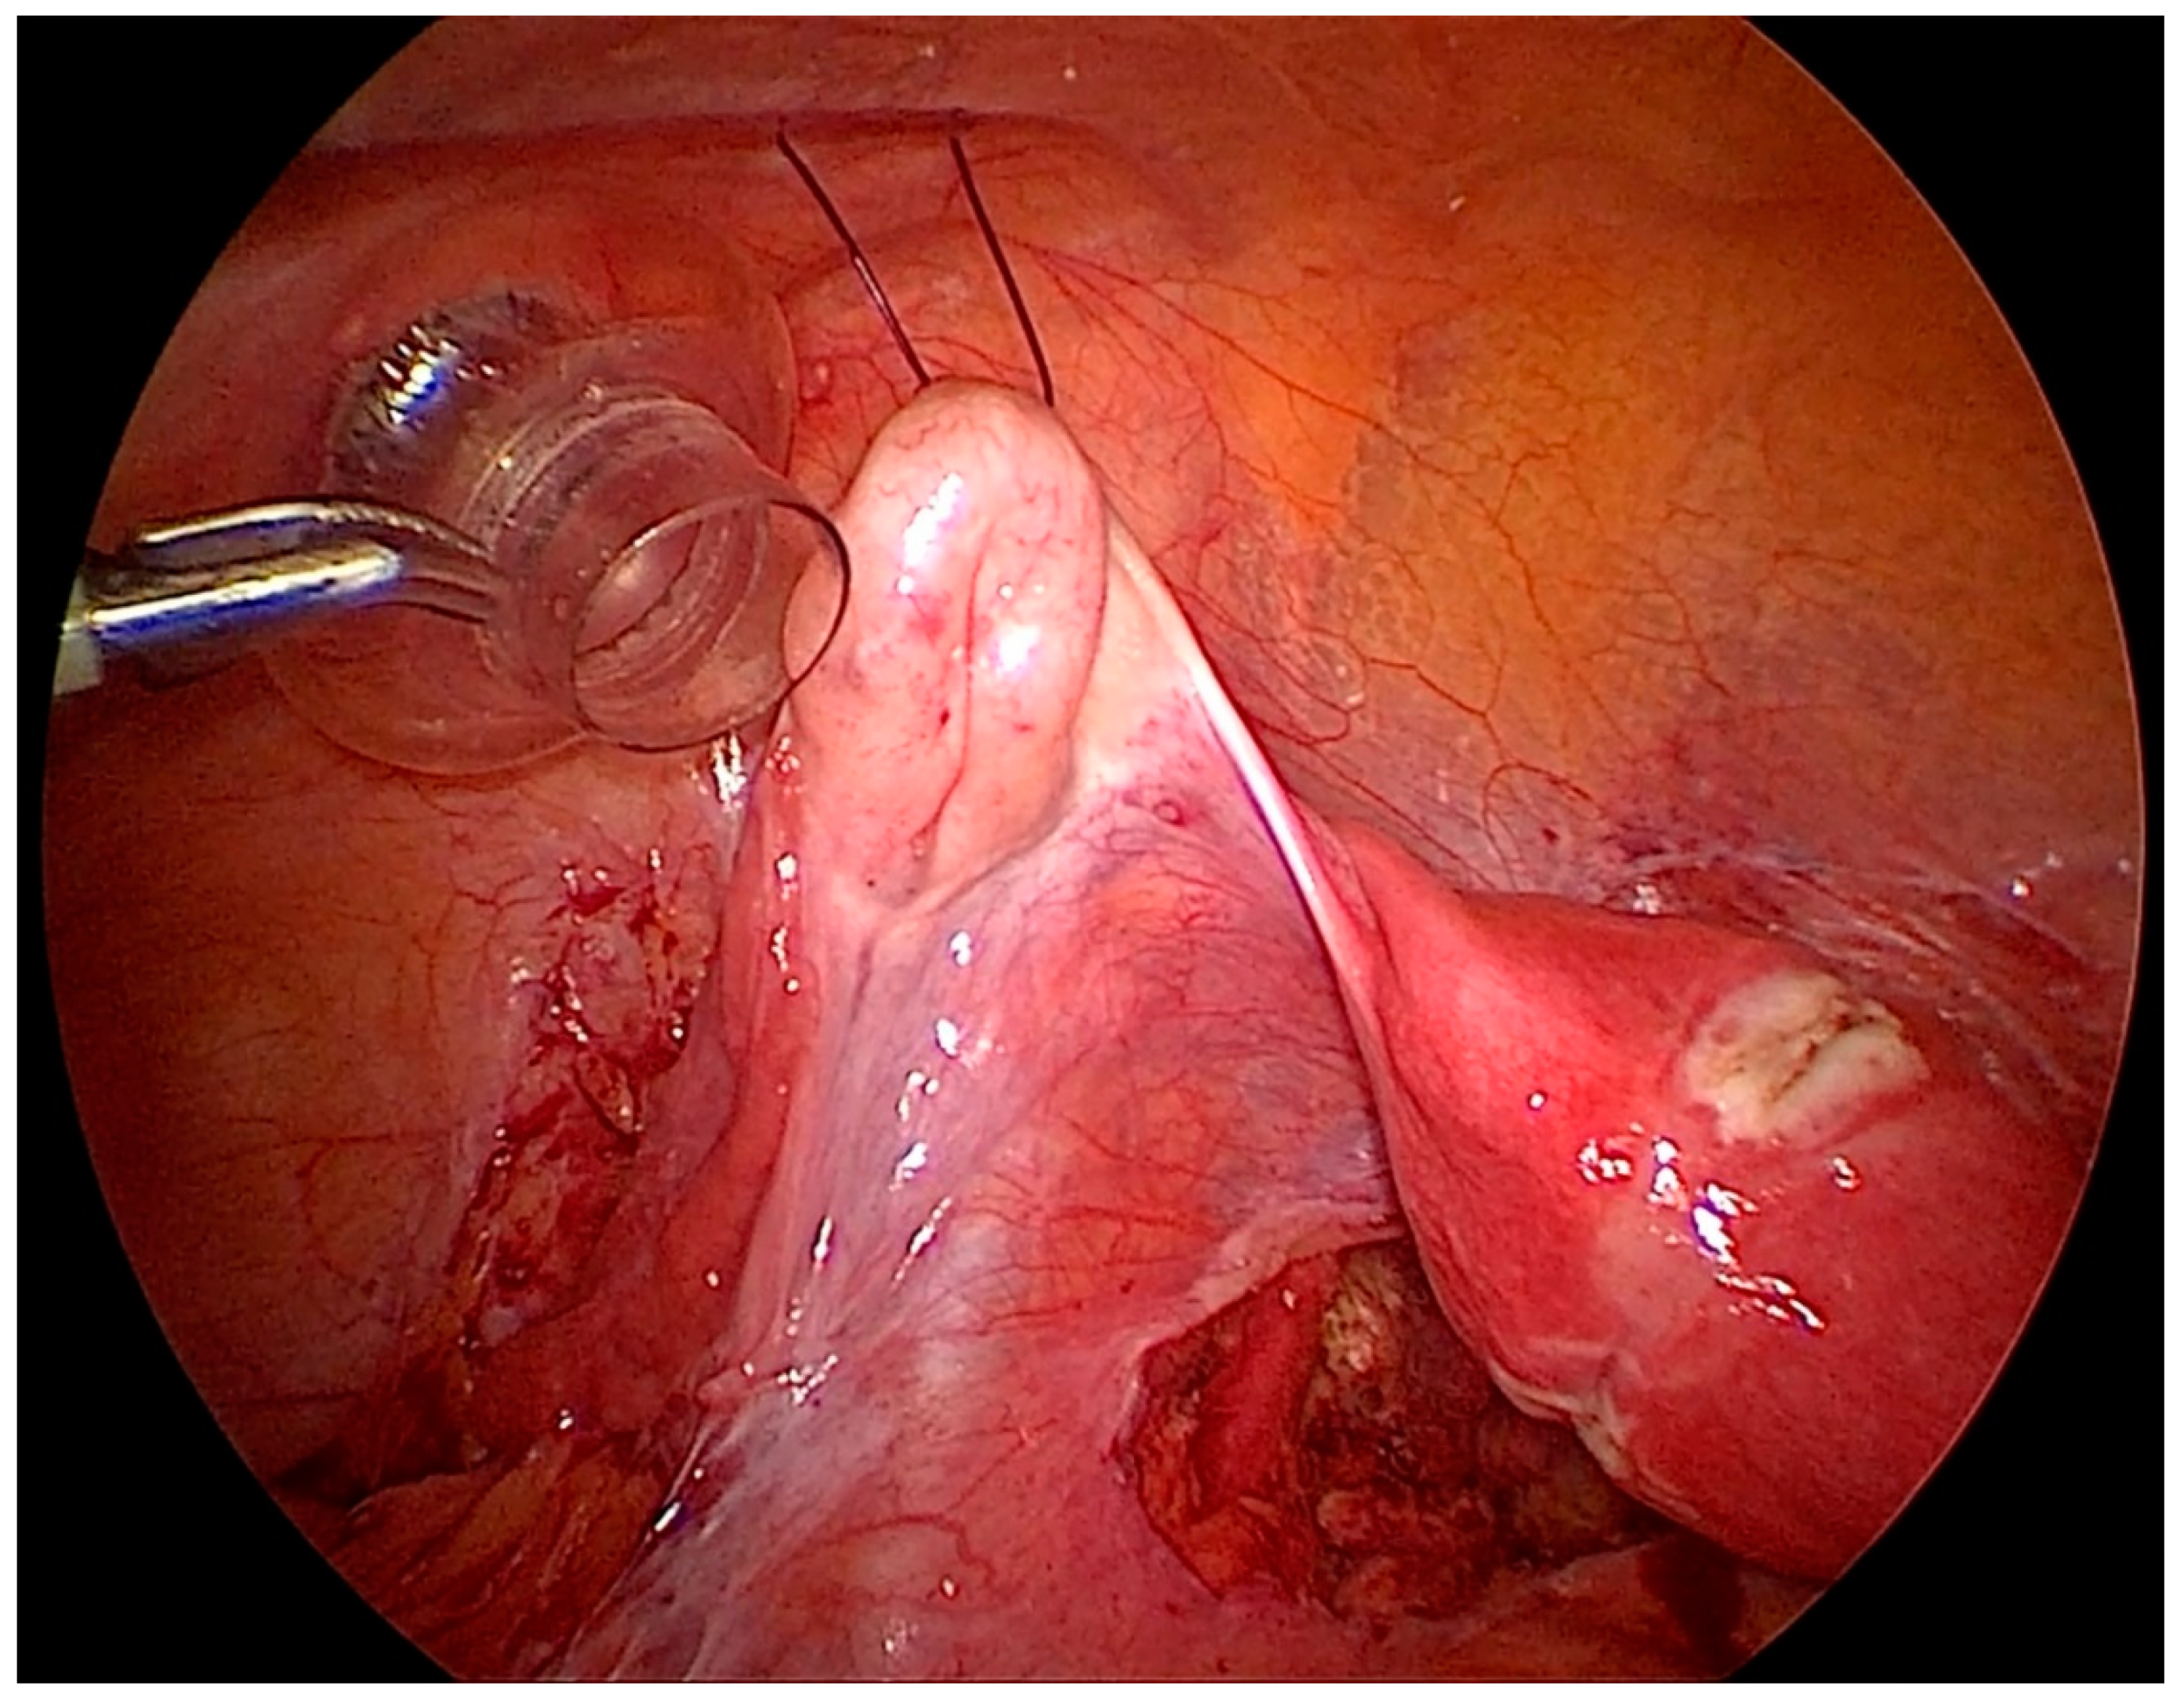

After gaining access to the peritoneal cavity laparoscopically (Figure 1), the cavity is thoroughly investigated for endometriotic cysts, spots, and adhesions. If an endometriotic ovarian cyst is found, it is excised. If endometriotic spots or nodules are found underneath the ovary on the ovarian fossa, or uterosacral ligaments, the ipsilateral ovary is suspended to the anterior abdominal wall (Figure 2). A straight needle with a single monofilament non-absorbable thread is passed through the lower anterior abdominal wall. Prior to insertion of the needle, the inferior epigastric vessels should be located to avoid injury and hematoma formation. The needle is retrieved intra-corporeally by grasping it using a laparoscopic needle holder. It is then passed from the medial side of the ovary through the ovary into the abdominal wall close to the point where it was introduced. At this step also, it is essential to pay attention to the inferior epigastric vessels once more. The needle is then pulled out from the abdominal wall using a hemostat forceps. The two ends of the thread are tied extra-corporeally over a compressor gauze on the abdominal wall, with some tension, thus suspending the ovary to the abdominal wall with the medial side of the ovary apposed to the peritoneum of the anterior abdominal wall (Video S1).

Figure 2. Laparoscopic view of the lateral pelvic wall on the left side after ovariopexy with endometriosis easily visualized and accessible.

Depending on the in-situ findings, unilateral or bilateral ovaries can be suspended.

After the procedure is complete, the ovarian suspension is loosened to maintain a gap of 1–2 cm between the ovary and the abdominal wall to prevent adhesions. This suspension is maintained for 5 days, and sutures are cut on the day 5th-day post-surgery (Figure 3).

Figure 3. Left side ovary suspended to the anterior abdominal wall, with dissection of the left lateral pelvic wall.

Another illustration after endometriosis resection with the important anatomical structures shown (Figure 4). Vessels in the abdominal wall have to be kept in mind before doing an ovariopexy to prevent puncture of it [29]. Comfortable access to the lateral pelvic wall is really important to prevent damage to major structures like the ureter and uterine artery, a very common site for superficial and deep endometriosis.